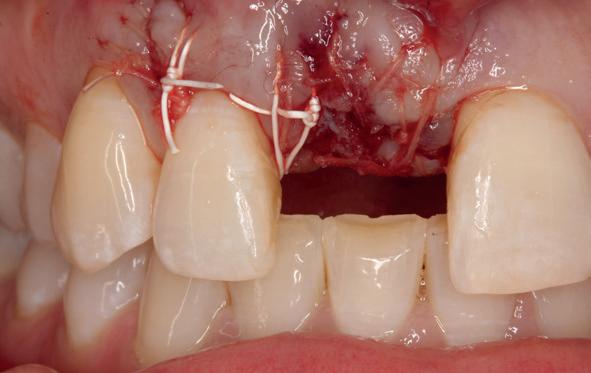

Lateraal van de implantaten wordt de kaak fors uitgebouwd volgens de Hybride GBR-techniek met Oragraft (allograft) van Lifenet die wordt vermengd tot een cocktail met BioOss (xenograft) van Geistlich, autoloog geoogste botsnippers en verzameld bloed uit het wondgebied. De botgraft wordt bedekt met een Ossix (crossed linked) membraan en met Hyadent (hyaluronzuur) overspoten. De sinuslift wordt gelijktijdig met de laterale botopbouw volgens de Caldwell Luc methode uitgevoerd en de uitgeprepareerde holte opgevuld met de botgraft. De flaps worden eerst horizontaal ontlast (gemobiliseerd) en vervolgens naar elkaar toe gehecht met vicryl rapide. Daarbij wordt gebruikgemaakt van horizontale matrassen, zodat de wondranden passief tegen elkaar

komen te liggen en de flaps primair gesloten kunnen worden. Het passief sluiten van een flap voorkomt wonddehiscenties in de genezingsfase die als complicaties kunnen optreden en botregeneratie verstoren. Daarnaast wordt bij een wonddehiscentie het risico op infectie van de graft sterk verhoogd waardoor het gewenste resultaat niet kan worden bereikt. Afstoting van graft materiaal komt dan veelvuldig voor soms gecombineerd met abcesvorming als geen voorzorgsmaatregelen worden genomen. Complicaties moeten daarom nauwlettend gevolgd worden totdat ze verdwenen zijn. De patiënt krijgt na chirurgie postoperatieve instructies en adviezen over de postoperatieve zorg. Daarbij wordt ook de nadruk gelegd op het koelen (coldpack) en zijdelingse druk op de wang. Het blijkt dat koelen en het uitoefenen van druk op het operatiegebied oedeem en hematoomvorming grotendeels kunnen verminderen en soms zelfs kunnen voorkomen.